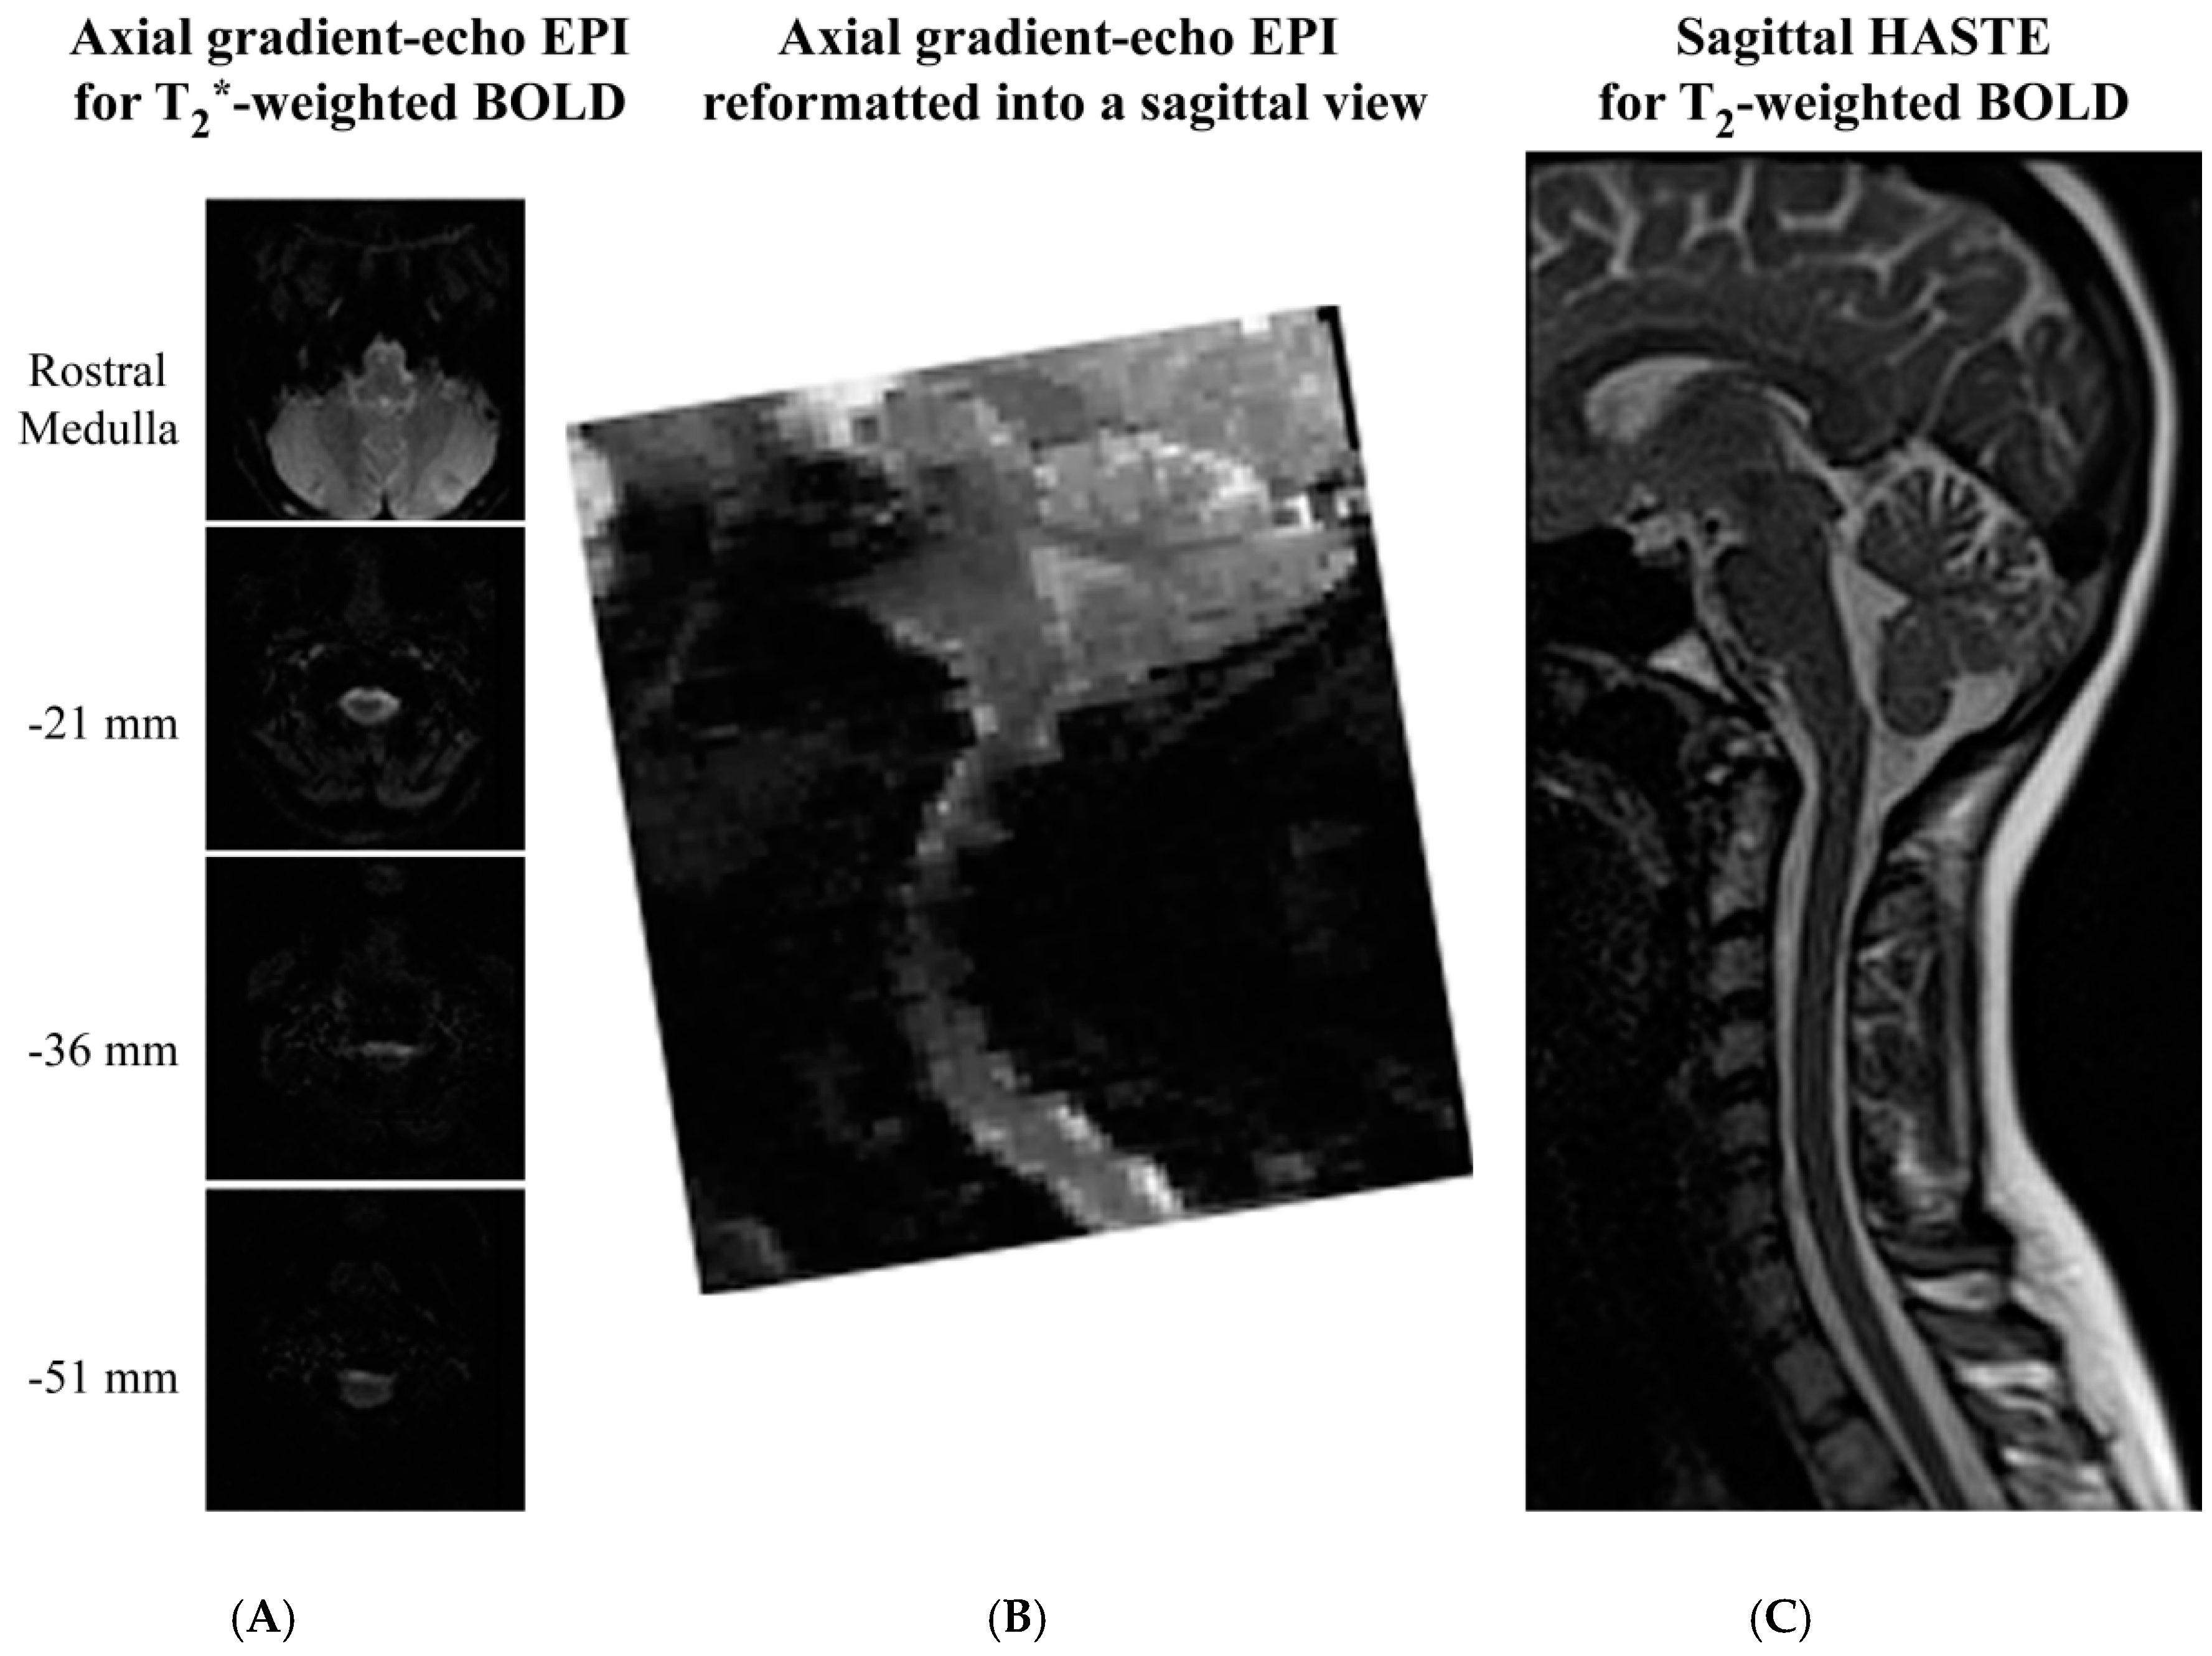

Figure 4.

Comparison of image quality obtained with gradient-echo EPI and spin-echo HASTE sequences for spinal fMRI. Gradient-echo EPI images were acquired in contiguous axial slices (A) and were reformatted into sagittal views (B) for comparison with spin-echo (HASTE) images acquired in sagittal planes (C). Selected axial slices are shown for comparison, and the slice positions are indicated relative to the caudal medulla (top slice). Images were acquired at 3 tesla with a Siemens MAGNETOM Trio at Queen’s University, and used as examples for this review.